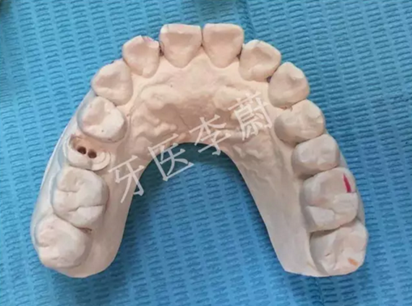

15牙模型